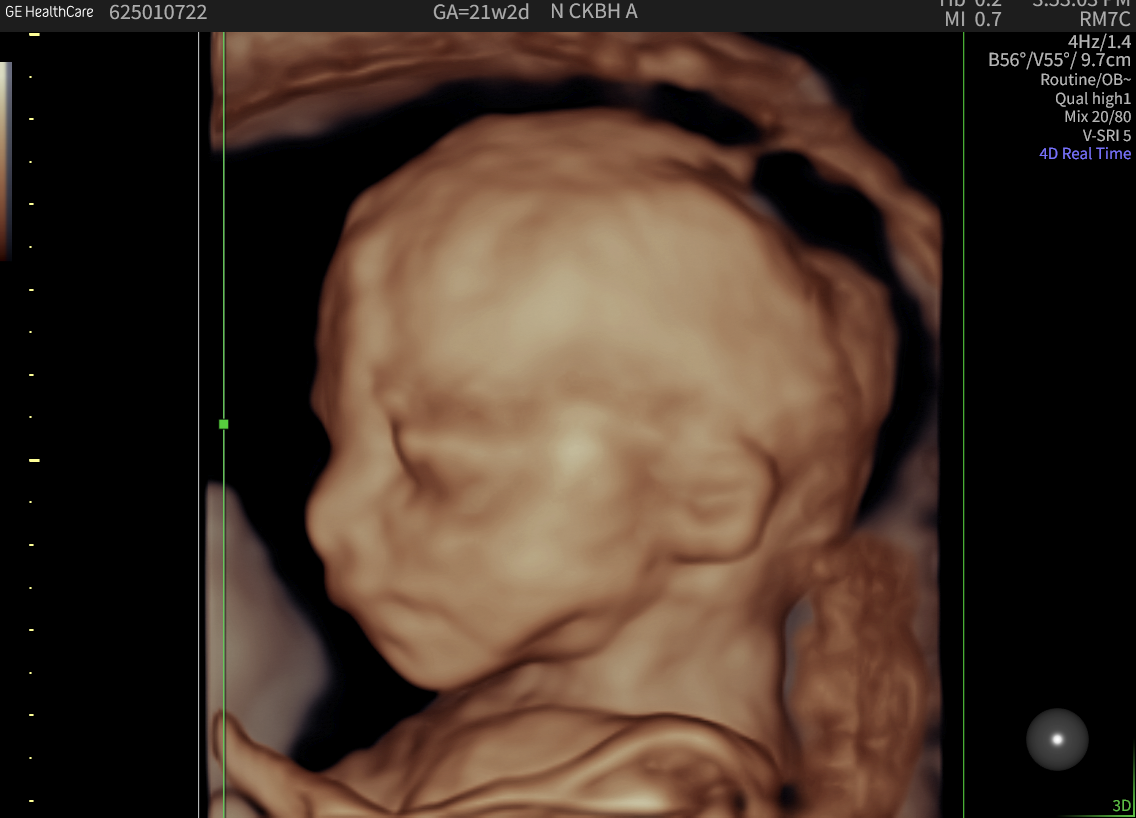

In ‘2D’ ultrasound, only a thin slice of the fetus is viewed at any one instant. This allows a lot of detail, and the person performing the ultrasound (the sonographer) mentally gets the third dimension by moving the probe. With 3D ultrasound, a whole series of slices are taken in quick succession. The slices are then put together to look more like a picture you would see with your eyes. To get the rapid multiple slices, each individual ultrasound slice contains diluted information.

4D is a description of 3D that tells you it is being performed live. Therefore, the fetal movement is seen.

The quality of 3D and 4D images depends on several factors, including the baby’s position, the amount of fluid around the face, and whether limbs or the umbilical cord are blocking the view. As with 2D ultrasounds, maternal build can also influence the image quality.

When the conditions are right, seeing your baby’s face in 3D can be an unforgettable experience for parents-to-be. However, it’s good to keep in mind that some minor distortions are a natural part of the imaging process.